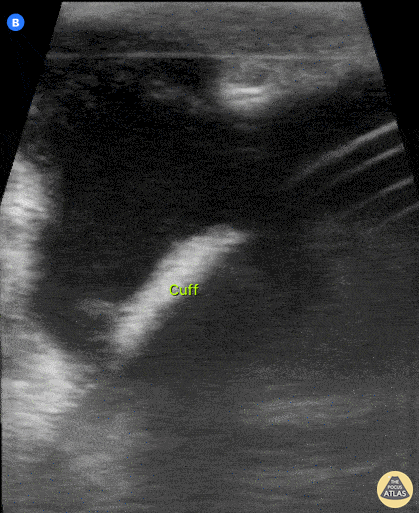

Pictured here is a the proximal cuff of an indwelling peritoneal catheter. Note the abscess surrounding the cuff. Javier Estrada, Nephrologist, Costa Rica